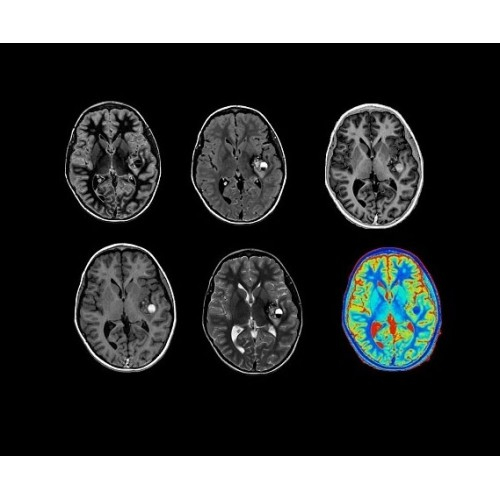

• Специальный пакет приложений для измерения и сравнения объемных изображений ЦНС с нормами поможет вам в диагностике нейродегенеративных заболеваний, а дополнительные инструменты визуализации — в постановке точного диагноза с помощью бета-амилоидов и радиоизотопных маркеров ФДГ.

• In vivo лаборатория — получайте полные данные биохимических процессов in vivo с мультиядерной спектроскопией на SIGNA PET/MR.